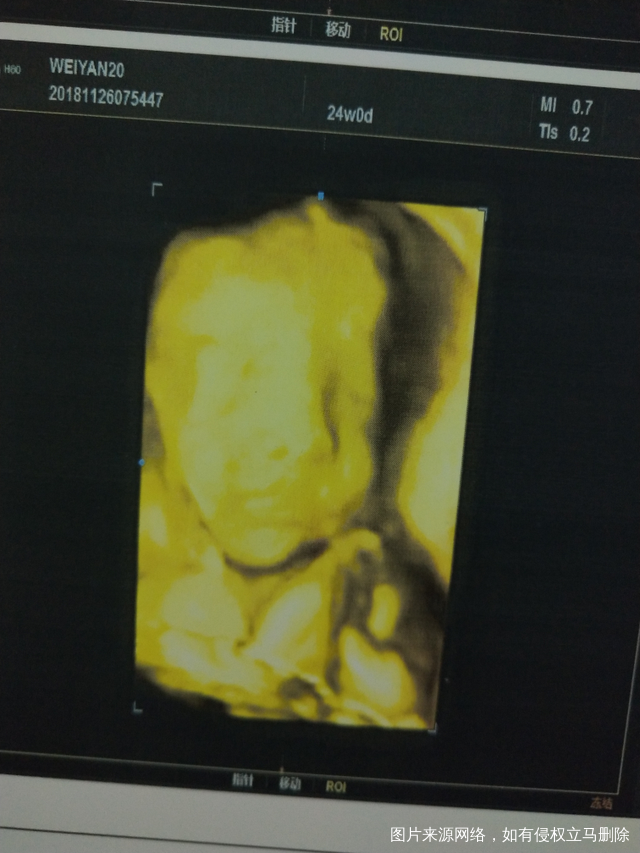

四维通过!恭喜我吧!顺便附上照片!!😃😃

5今天早上我是第一个照,起了个大早,觉也没睡好,跟你爸爸一起吃了三块钱的酱香饼,第一次有点趴着,医生一动你你就变得更趴了大概40几分钟失败了,好吧,带着你吃了根棒棒糖🍭,破例买了奶茶🍵,又吃了一碗不辣的肉丝酸辣粉🍲,爬了八层楼🏃,累得我喘大气啊!第二次还是趴着照了两分钟还是又失败了,医生叔叔又叫我去旁边的空铺侧躺🙇,大概半小时,又照依旧失败,出去有点小失望了,晒了会儿太阳☀,回来让你老爸买了巧克力🍫吃,喝了开水🍶,第三次医生又是摇又是使劲揉啊,你妈妈我的肚子都疼起来了,还是失败了,好吧,吃了个青椒土豆盖饭🍛后,又回来,继续照,医生叔叔吃了外卖继续照,结果依旧失败!你妈子我开始各种担忧啊!你老爸明天还不能陪我,有活要干了,我就在车里前排座位各种把你头头转出盆骨的方法都用尽了,之后在车里又小憩半小时午觉,结核医院跟你老爸查了痰之后又去妇幼保健院,一直我都撅着屁股,生怕你小脑袋不出盆骨,照之前又是一顿担忧☹️,进比超室最后一次,女医生阿姨告诉我你出盆骨了,能看得到,但是手挡住了脸,各种摇你,妈妈也各种说你要听话哦,乖乖的哦,给医生露个脸就带你吃好吃的,这次你学聪明了,终于露了脸!我好开心😘,两个医生都笑你了😁!嗯!最后顺顺利利的,照得算好的!很满意!去结核医院结果也都是好的,

你们说,这娃娃像男孩👦还是女孩👧呢!?😋😋😋